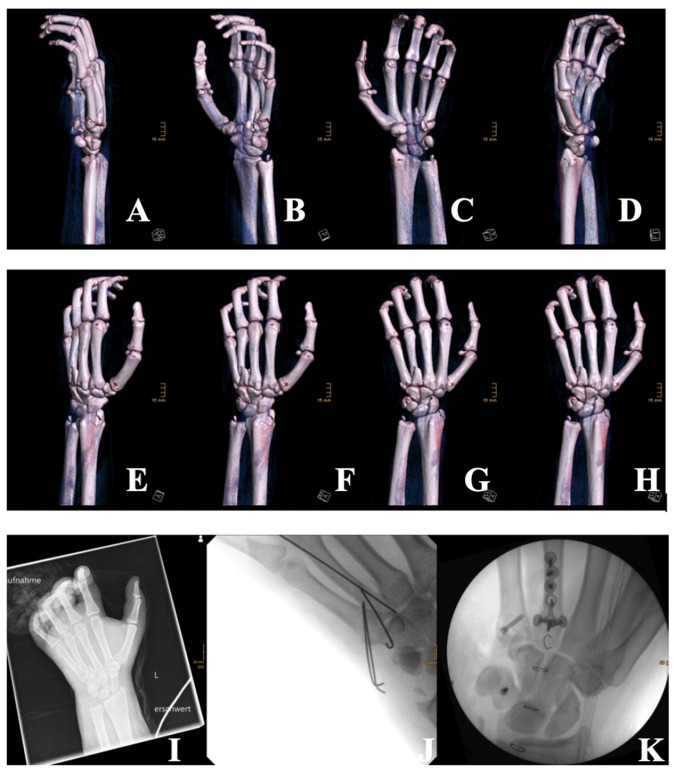

在德国,与工作有关的火灾伤害仍然是一个严重的公共卫生问题,特别是在新年前夕。虽然许多伤害是轻微的,但滥用非法或自制烟花可能造成类似军事战斗伤害的严重创伤,并可能给应急服务造成沉重负担。值得注意的是,在2019冠状病毒病烟花禁令期间,受伤率有所下降,凸显了预防措施的效果。我们报告两例年轻男性严重伤害从非法烟花。第一个案例是一个16岁的孩子,他引爆了一枚非法的波兰烟花球炸弹,造成全身表面积9%的烧伤(二到三度),手部骨折,手部筋膜室综合征和软组织损伤。他接受了多次手术,包括筋膜切开术、骨融合术和植皮术。另一个案例是一名19岁的男子,他被一个由鞭炮捆扎而成的自制装置炸伤,面部和双手被深度烧伤。患者需要延长通气时间,手术清创,并用Kerecis®鱼皮和Epicite®敷料治疗。两者都需要重症监护、跨学科管理和漫长的康复。按照标准化的德国DRG计算,医院费用总额分别为58 459.52欧元和94 230.23欧元。这些案件说明了非法燃放烟花爆竹的破坏性影响。爆炸性创伤的破坏性后果往往难以治疗,并可能导致长期的功能和心理损伤。通过公共教育、更严格的法规和准备进行预防至关重要。大流行时期减少伤害支持持续的政策努力。

Firework-related injuries remain a serious public health issue in Germany, especially during New Year's Eve. While many injuries are minor, the misuse of illegal or homemade fireworks can cause severe trauma resembling military combat injuries and can heavily burden emergency services. Notably, injury rates declined during the COVID-19 firework bans, underscoring the impact of preventive measures. We report two cases of young males with severe injuries from illicit fireworks. The first is a case of a 16-year-old that detonated an illegal Polish firework ball bomb, sustaining 9% total body surface area (TBSA) burns (second- to third-degree), hand fractures, compartment syndrome of the hand, and soft-tissue trauma. He underwent multiple surgeries, including fasciotomy, osteosynthesis, and skin grafting. The other case presented is a 19-year-old man who was injured by a homemade device made of bundled firecrackers, suffering deep facial and bilateral hand burns. He required prolonged ventilation, surgical debridement, and treatment with Kerecis® fish skin and Epicite® dressings. Both required intensive ICU care, interdisciplinary management, and lengthy rehabilitation. Total hospital costs amounted to €58,459.52 and €94,230.23, respectively, as calculated according to the standardized German DRG. These cases illustrate the devastating impact of illegal fireworks. The devastating consequences of explosive trauma are often difficult to treat and may lead to long-term functional and psychological impairments. Prevention through public education, stricter regulations, and preparedness is essential. Pandemic-era injury reductions support sustained policy efforts.